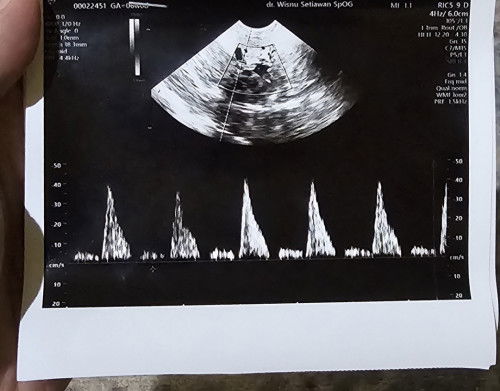

Barusan USG perut di puskesmas. Sedih banget enggak keliatan janinnya. ๐ฅฒ Tapi aku emang gemuk sih bun, perutku udah buncit sejak sebelum hamil. Minggu depan mau USG transvaginal di obgyn deh. Soalnya pas 7 weeks aku pernah USG transvaginal udah lihat janin kedut-kedut tapi belum bisa denger djj-nya (alatnya kurang canggih). #Sharingdong_Bund